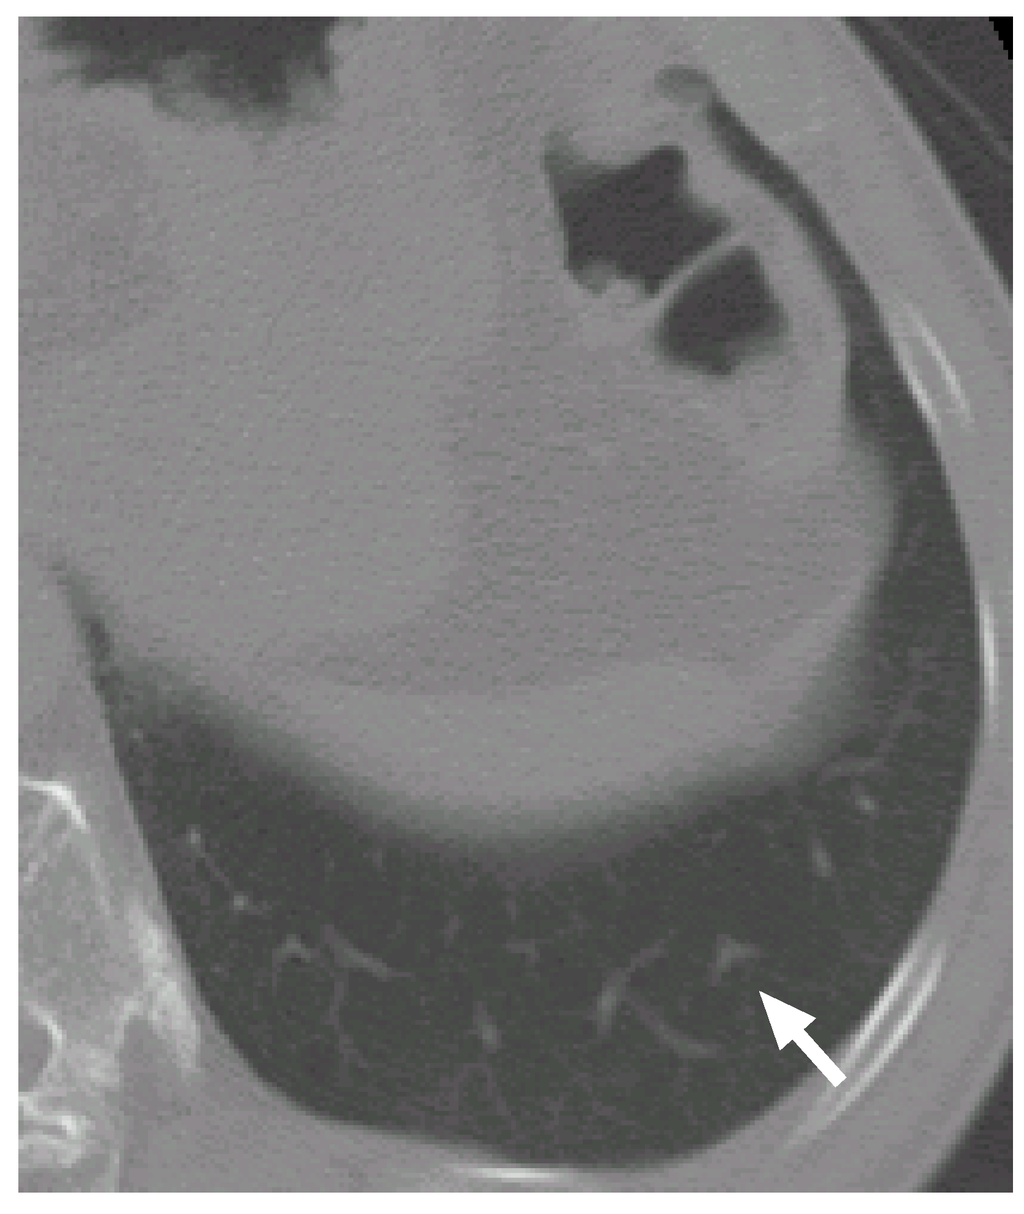

Figure 6 shows a slice cross section of a sample CT scan. The arrow indicates a nodule identified by a radiologist. The nodule is detected by our previous methods [8,27,28] as a nodule candidate. Figure 7 (a–c) shows a VOI of the nodule (Figure 7(b) shows the nodule). Figure 7(d–f) is template produced from the most likely nodule model that is depicted in Figure 8(a). They correspond to Figure 7(a–c), respectively. Figure 7(g–i) is produced from the most likely curved blood vessel model depicted in Figure 8(b), and Figure 7(j–l) is produced from the most likely bifurcated blood vessel model depicted in Figure 8(c). They correspond to Figure 7(a–c), respectively, in the same manner.

Figure 6. A slice cross section of a sample thoracic CT scan. The arrow indicates a nodule identified by a radiologist.

The posteriori probabilities of the most likely object models o N , o B c and o B b are 0.124, 0.087 and 0.100, respectively (the common constant values are omitted), and the ratio of the posteriori probabilities ρ 1 is 1.24. Because the ratio is larger than the threshold T ρ , the nodule candidate is correctly determined to be a nodule.

The nodule (Figure 7(a–c)) is faithfully reconstructed by the templates (Figure 7(d–f)). Although the nodule is shifted downward against the VOI (the nodule is not observed in the upper slice section shown in Figure 7(a)), the center of the nodule model is moved adequately. The nodule size is also estimated exactly. The diameters of the nodule and the nodule model are approximately 5.0 mm and 5.3 mm, respectively.

The effectiveness of Equation (3) can be seen in the templates of the curved and bifurcated blood vessel models shown in Figure 7(g–i) and (j–l), respectively. Because the nodule candidate is in the peripheral area of the lung region (see Figure 6 again), the mean radius of a blood vessel model μ r 1 B ( x B c ) becomes rather small, 0.89 mm, at this position. The small mean radius produces thin regions on the templates and the thin regions make the correlation coefficients low. Therefore, the probabilities of the blood vessel models become smaller than that of the nodule model.